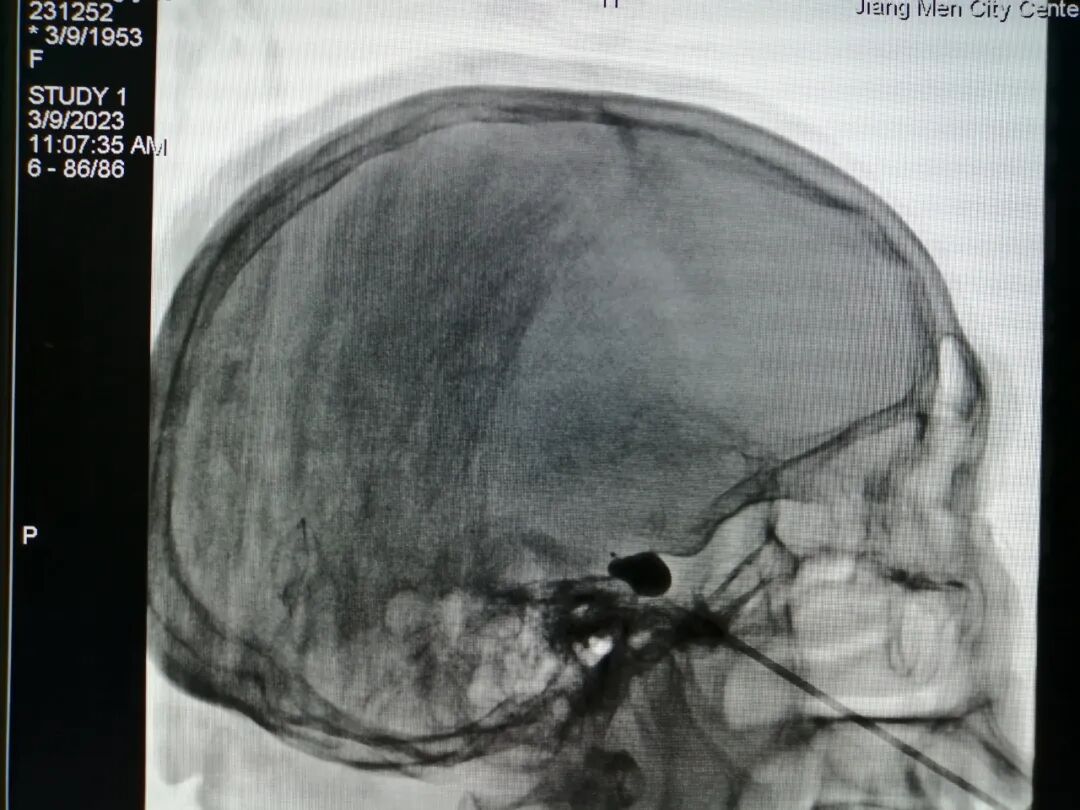

△三叉神经半月节微球囊压迫术

△三叉神经半月节电刺激植入术